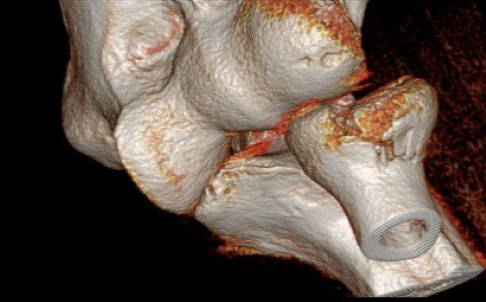

Computertomografie (CT), digitale Volumentomografie (DVT) und Magnetresonanztomografie (MRT)

Ist der Bruch nicht sicher im Röntgenbild zu beurteilen oder liegt ein komplizierter Bruch oder gar eine Zertrümmerung des Radiusköpfchens vor, erfolgt zusätzlich eine Computertomografie (CT)/digitale Volumentomografie (DVT).

Diese Untersuchungen ermöglichen eine eindeutige Einteilung des vorliegenden Bruchs und die Darstellung von möglicherweise vorhandenen knöchernen Begleitverletzungen. Der Bruch des Processus coronoideus ist ein wichtiger Hinweis für ein instabiles Ellenbogengelenk. Dieser knöcherne Vorsprung der Elle stabilisiert das Gelenk neben dem Radiuskopf nach vorne.